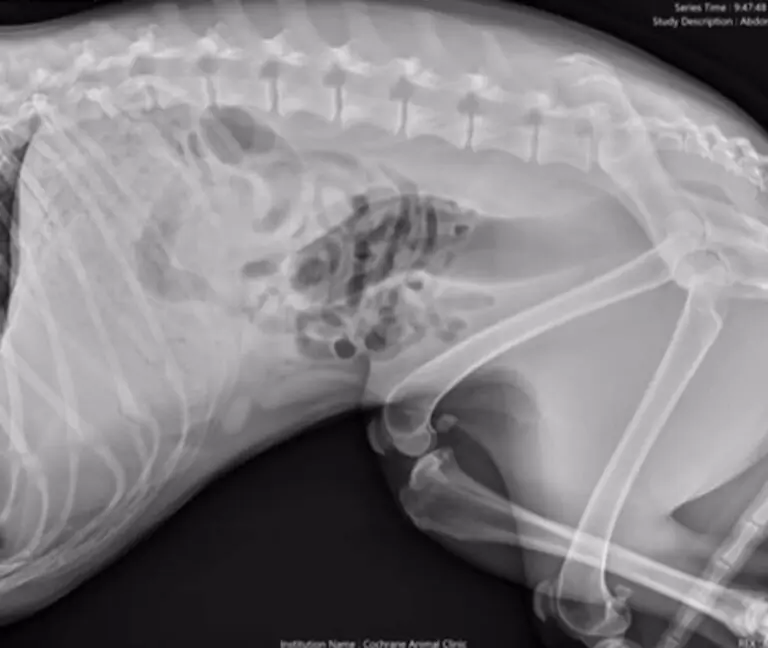

Little did they know, Stella had been up to some mischief. An X-ray revealed a shocking truth: their furry friend had ingested eight pairs of underwear!